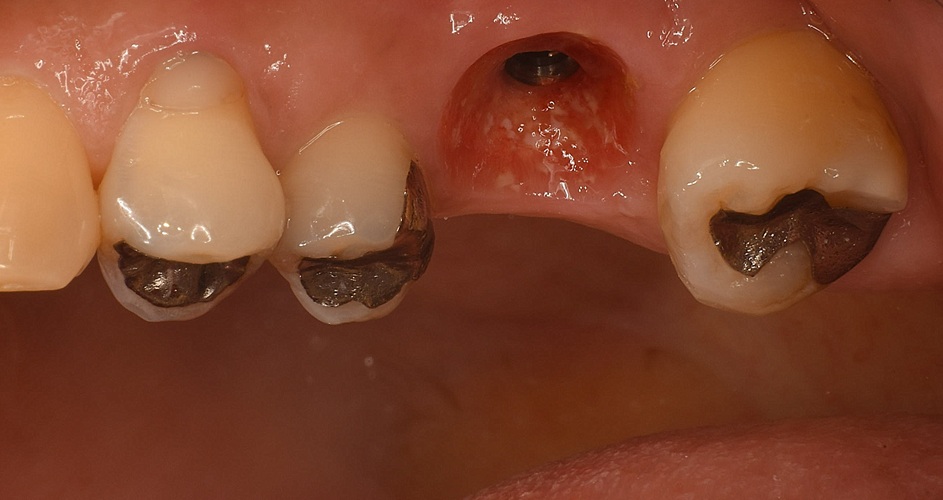

Case6

| 治療名 | 抜歯即時インプラントによる審美的回復症例 |

| 治療説明 |

歯の根が割れてしまったことにより、抜歯が必要となった症例です。 インプラント周囲の骨の一部に吸収が見られたため、小規模な骨造成(GBR)を併用しました。 |

| 治療回数・期間 | 約3ヶ月 |

| 副作用とリスク | ・入れ歯や従来のブリッジに比べて治療期間が長くなることがあります。 ・骨造成を伴う場合、さらに期間が延びることがあります。 ・インプラント手術後には一時的に痛み、腫れ、出血、違和感などが生じることがありますが、多くは数日〜1週間程度で治まります。 |

| 料金(税込) | 小規模GBR:110,000円 インプラント一次手術:220,000円 二次手術:55,000円 上部構造〈セラミック〉:165,000円 合計:550,000円 |